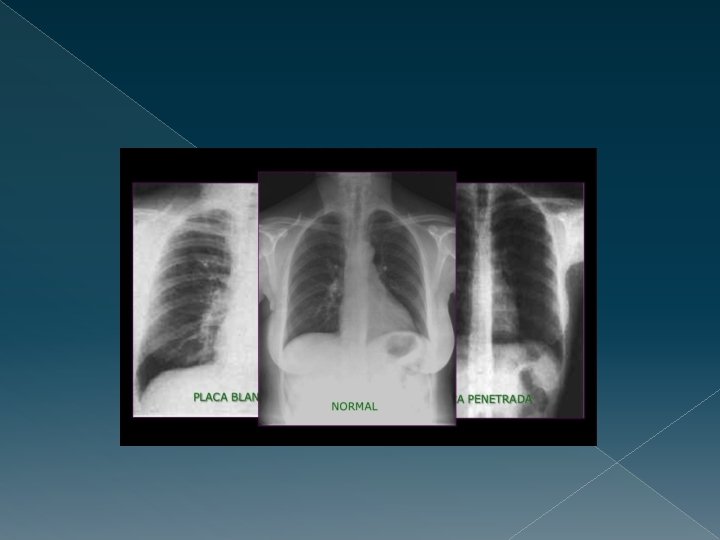

VALORACIÓN DE LA TÉCNICA Comprobar si técnicamente es adecuada. 1. Penetración adecuada › BIEN PENETRADA: El parénquima tiene aspecto grisáceo y vemos algunos discos vertebrales a través de la silueta cardíaca. › DURA O MUY PENETRADA «quemada» : El pulmón se ve negro, y los discos vertebrales retrocardíacos se distinguen muy bien. › BLANDA O POCO PENETRADA: El pulmón se ve muy claro, y no se ven los discos vertebrales retrocardíacos.